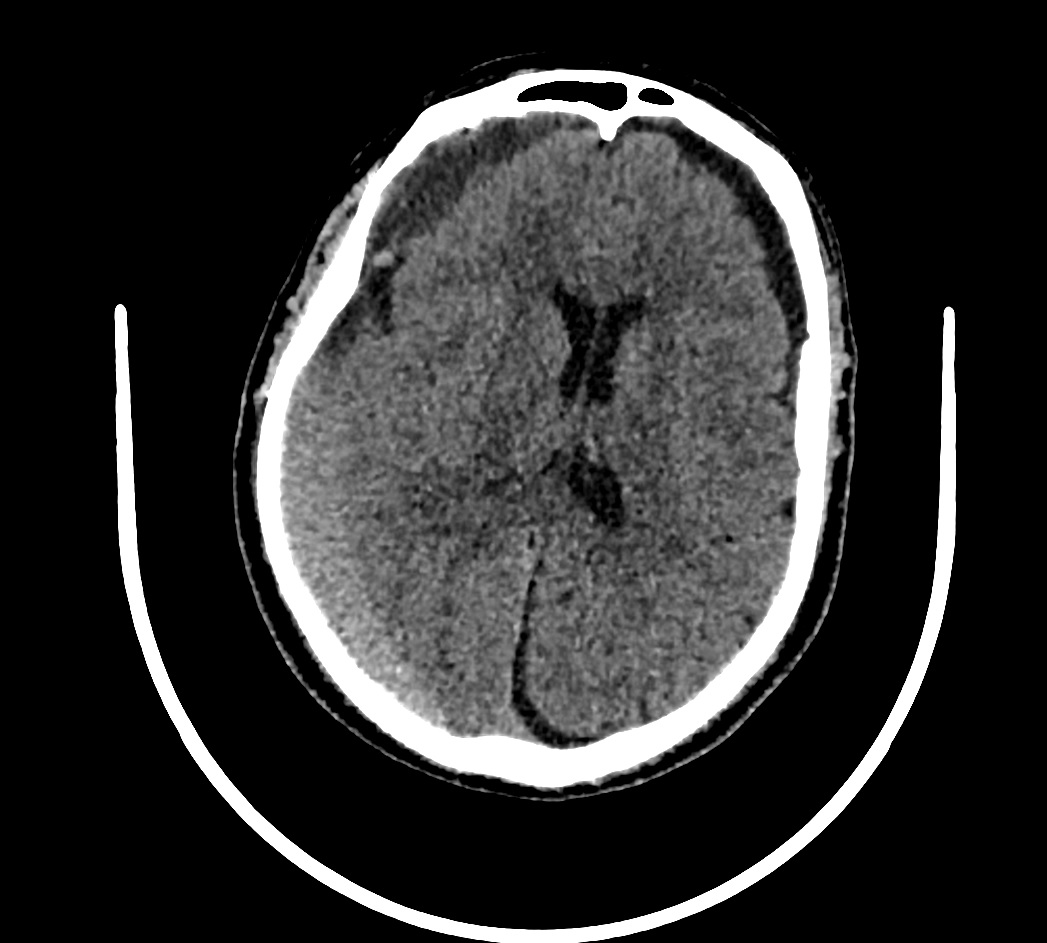

TAC cráneo: Hematoma subdural subagudo-crónico y efecto compresivo con obliteración de surcos frontoparietales.

Último TAC de control: Resolución del HSD derecho.